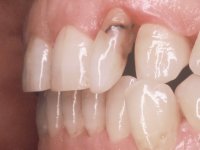

A paciente queixava-se que tinha um dente da frente a abanar, não gostava do “canino escuro” e também “queria fechar os espaços entre os dentes”. Passados 8 anos do tratamento inicial, o que motivou uma segunda fase de tratamento foi os “dois dentes da frente estarem feios”. Um ano após a última intervenção, apareceu um terceiro motivo para a terceira fase de tratamento, que foi a fratura da faceta feldspática colocada no dente 2.1.

Paciente do sexo feminino, com 47 anos não fumadora. Apresentou-se na consulta com o dente 1.3 com tratamento endodôntico e com um espigão falso coto fundido, reabilitado com uma coroa provisória. Os dois incisivos laterais superiores são conoides e de reduzida dimensão. O dente 2.2 apresenta mobilidade, consentânea com uma significativa reabsorção óssea entre o dente 2.1 e o dente 2.3 Os dois incisivos centrais estão separados por um diastema de 3mm e o dente 2.3 apresenta uma oclusão cruzada com o dente antagonista. Verifica-se também a ausência de alguns dentes posteriores e uma higiene oral razoável. Na segunda intervenção realizada passados 8 anos, verificou-se que os incisivos centrais superiores se apresentavam cromaticamente mais escuros e apresentavam um sulco longitudinal no esmalte que estando pigmentado comprometia esteticamente o sorriso. O trabalho realizado na primeira fase do tratamento mostrava-se competente estética e funcionalmente. Por fim, um ano após a última intervenção, a paciente apresentou-se com uma fratura da faceta colocada no dente 2.1 provavelmente em resultado de estar em contacto com o coto do implante. A rigidez da anquilose implantar, pode ter sido a causa desta fratura. Outros casos deste tipo de fratura já foram observados por mim em situações clínicas idênticas. A faceta do dente 1.2 apresentava-se esteticamente comprometida e a própria estrutura dentária apresentava uma pequena cárie e, pelo que se recomendaria a sua substituição.

• Confeção e colagem de uma nova faceta feldspática para substituir a fraturada. A nova faceta deverá incluir maior área dentária inter-proximal distal do dente 2.1.

• Substituir a faceta do dente 1.2 por uma coroa total em cerâmica feldspática ou por uma, agora denominada, faceta 360.

O tratamento iniciou-se com a re -preparação do coto do espigão falso coto fundido, com o objetivo de colocar as linhas de acabamento cervical com uma localização intra-sulcular e simultaneamente confecionar uma coroa provisória adaptada. Com um tratamento ortodôntico muito simples, fechou-se o diastema entre os incisivos centrais superiores e estabilizou-se esta posição com um arame colocado na superfície palatina dos centrais, funcionando como contenção. Posteriormente procurou-se fazer uma tração ortodôntica lenta do dente 2.2 com o intuito de diminuir, ainda que muito ligeiramente a perda óssea vertical nessa zona. Finalizada a tração, foi feita a extração do dente 2.2 e a zona foi reabilitada provisoriamente com uma coroa de resina composta colada aos dentes adjacentes. Foi colocado um implante dentário na zona do dente 2.2 sendo novamente colada a coroa provisória em resina, reabilitando provisoriamente a paciente durante o período de osseointegração. No dente 1.3 foi feita uma gengivectomia com bisturi elétrico, com a intenção de subir o nível cervical do 1.3 conseguindo uma maior harmonia com o dente 2.3. Estabilizados os tecidos moles, foi feita uma impressão com a técnica de moldeira aberta, utilizando silicones de adição de consistência “putty” e “light”. A recolha da cor, tanto da componente dentária como dos tecidos moles foi feita pelo ceramista no consultório.  No laboratório as impressões foram passadas a gesso e deram origem a modelos de trabalho que foram devidamente analisados. Foi decidido confecionar um “abutment” metalo-cerâmico aparafusado sobre o implante. Este “abutment” foi fundido com uma liga nobre e posteriormente revestido a cerâmica coronária e gengival. Dada a inclinação do implante o aparafusamento condicionou de forma inevitável a saída do orifício do parafuso pela superfície vestibular. No sentido de esconder esta situação, o desenho do “abutment” já foi idealizado com a intenção de acomodar na superfície vestibular a colagem de uma faceta feldspática. Este “abutment” foi provado em boca e foram feitos ajustes no componente cerâmico gengival. A sua adaptação aos tecidos moles foi feita tanto de forma subtrativa, com broca, como de forma aditiva, acrescentando resina composta de tonalidade gengival. Este acrescento de resina seria orientador do ceramista na colocação final da cerâmica de tonalidade gengival. A coroa que reabilitaria o dente 1.3 foi cimentada nesta consulta de prova com cimento de ionómero de vidro reforçado com resina composta. Finalizado o trabalho em laboratório da faceta sobre o 1.2 e o “abutment” e a faceta para o implante este foi colado em boca, após a colocação do isolamento absoluto. O trabalho satisfez plenamente a paciente. Durante oito anos a paciente foi seguida regularmente, mostrando-se agradada com o tratamento efetuado, no entanto começou a mostrar interesse em intervir esteticamente nos incisivos centrais superiores. Decidida a segunda fase da nossa intervenção, foi feita a preparação dentária dos dentes 1.1 e 2.1 para a colocação de duas facetas feldspáticas. Particular cuidado foi tido na preparação inter-proximal distal junto ao “abutment” do implante. Foi preciso avaliar muito pormenorizadamente o eixo de inserção da faceta em relação ao “abutment”. As facetas feldspáticas foram confecionadas em laboratório e posteriormente coladas em boca após a colocação de isolamento absoluto. Um ano após, iniciamos a nossa terceira fase de tratamento, após a faceta colada no dente 2.1 ter fraturado. A preparação dentária foi feita sobre a faceta colada, procurando estender mais para palatino o interface inter-proximal distal. O objetivo seria passar para mais palatino do ponto de contacto o interface faceta-dente. O preparo dentário do dente 1.2 também foi muito reduzido, limitando-se a criar um eixo de inserção. Após confecionadas a coroa total e a faceta em laboratório foram coladas em boca. Primeiro foi colada a coroa utilizando-se um isolamento relativo com teflon, posteriormente foi colada a faceta após a colocação do isolamento absoluto. Na coroa utilizei este tipo de isolamento para evitar a utilização de grampos. Seria difícil de aplicar pela forma e dimensão do dente e agressivo para os tecidos moles. Após a colagem foi avaliada a integração oclusal do trabalho.